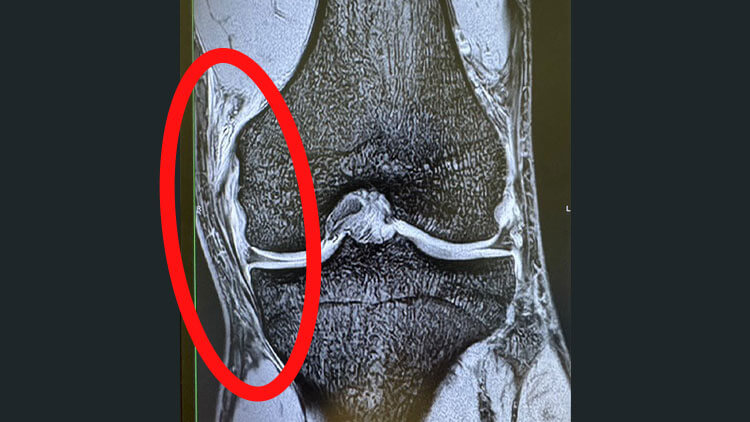

Case02

全治6ヶ月

選手生命に関わる靭帯断裂

競技からの長期離脱で

選手生命すら危うい状態から

たった1ヶ月半で競技復帰!

Before

少し動かすだけで激痛が走り

日常生活すら困難

After

出場は難しいといわれた

半年後の全日本大会も

万全の状態で出場予定!